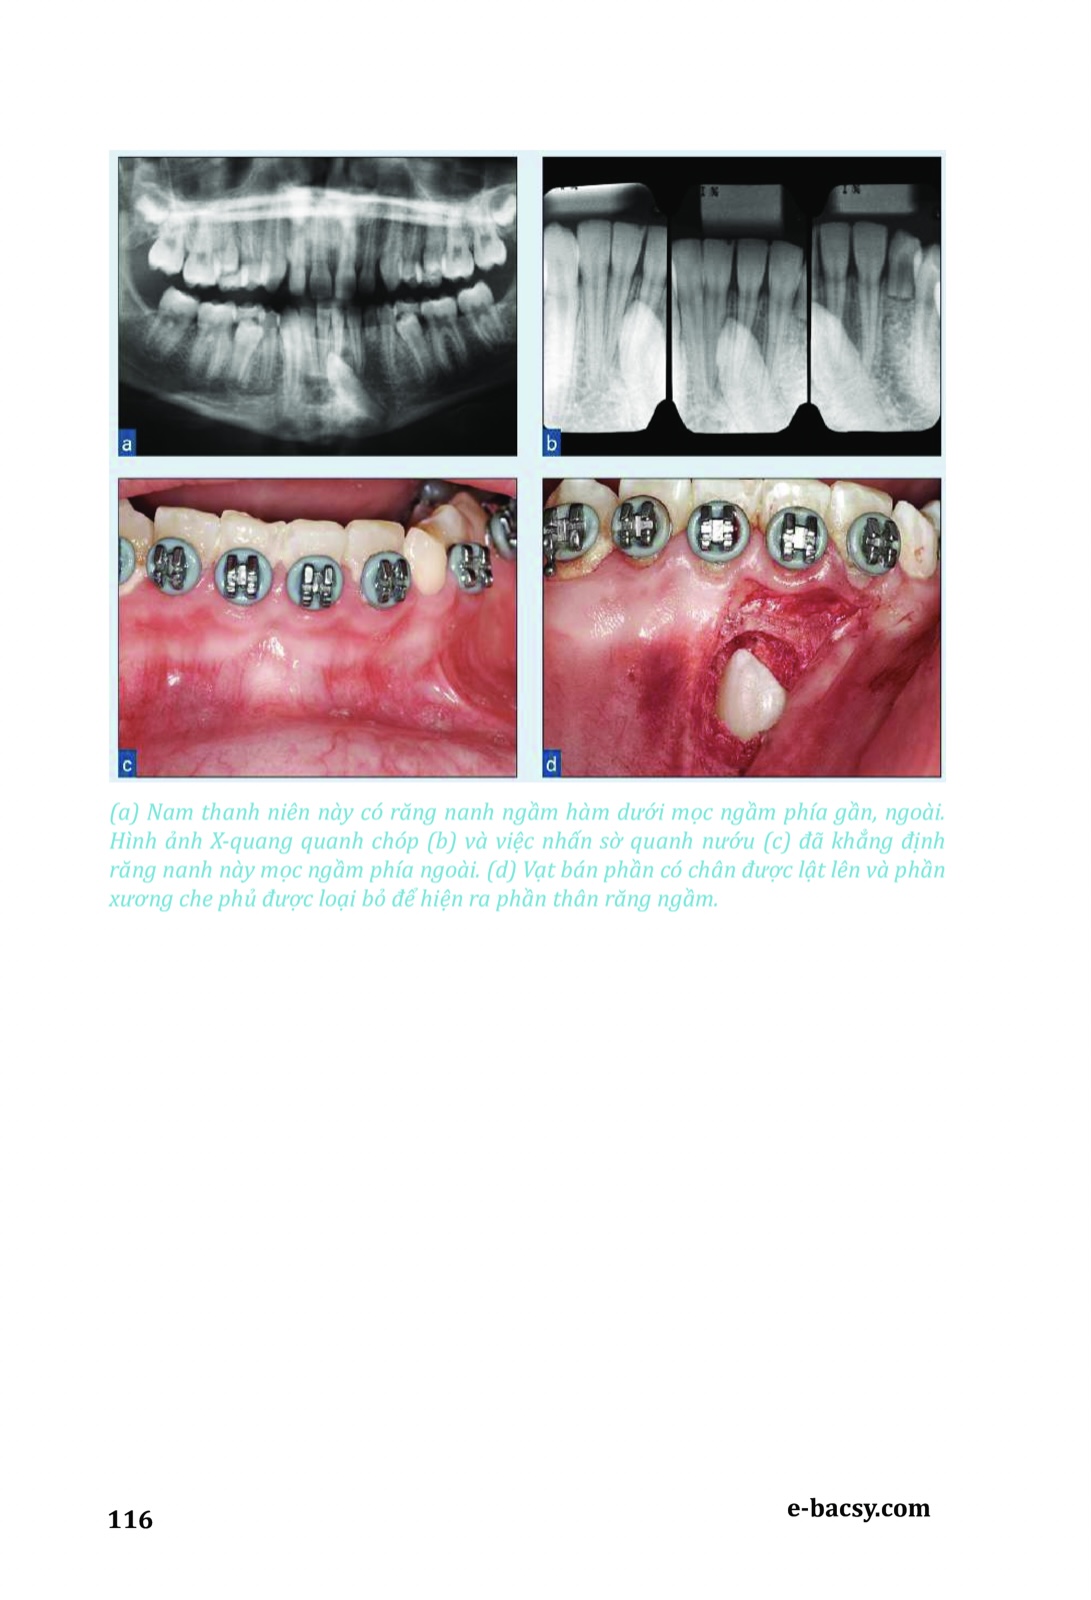

Răng mọc ngầm - Phẫu thuật cùng chỉnh nha